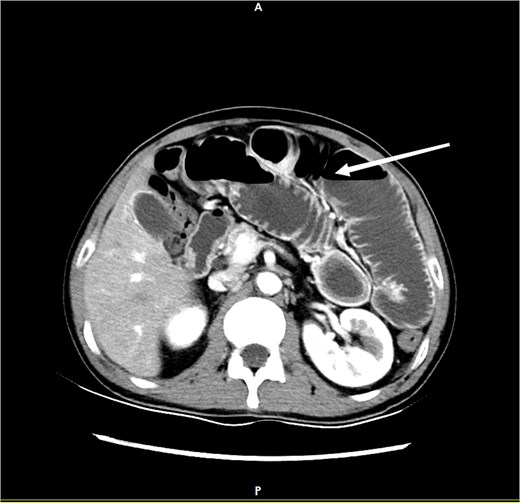

The patient, male, 48 years old, rural household registration. The patient was admitted with persistent epigastric pain and discomfort lasting over 5 days. He had a 3-year history of diabetes mellitus, regularly managed with oral metformin, and maintained good glycemic control. He had a history of diabetes for 3 years, regularly took metformin orally, and his blood glucose was well controlled. The patient complained of persistent abdominal pain and discomfort after eating 5 days ago, with abdominal distension and occasional nausea, no vomiting, diarrhea, hematochezia, acid regurgitation, hiccups, belching, chills, and fever. Since the onset of the disease, the patient's spirit, appetite, and sleep were poor, no stool, and normal urination. The weight did not drop. The physical examination showed normal temperature, slightly raised upper abdomen, visible intestinal type, no peristalsis wave, total abdominal tenderness (+), mainly in the upper abdomen, no muscle tension and rebound pain, mobile murmur (−), bowel sound hyperactivity, and the sound of air over water could be heard. Auxiliary examination: abdominal computed tomography (CT) suggested: gallbladder stones, intestinal obstruction, and uneven thickening of intestinal wall (Fig. 1).

CT demonstrates features of intestinal obstruction as marked by the white arrow.